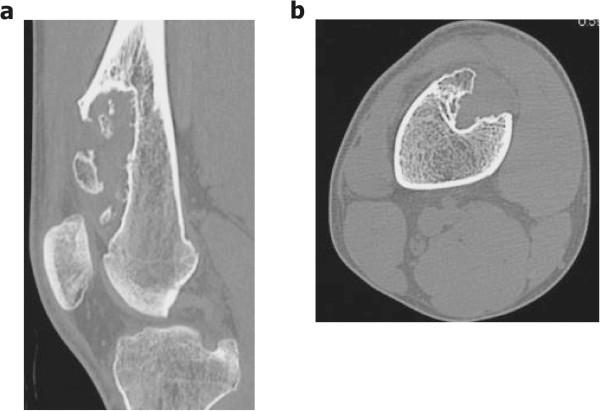

Periosteal chondromas are rare benign cartilaginous tumors that arise adjacent to the cortex beneath the periosteum. These lesions are usually slow-growing and rarely exceed 3 cm in the greatest dimension. Here, we describe a 17-year-old boy who had a giant periosteal chondroma of the right distal femur, which was treated with intralesional resection and intensive curettage. In addition, we report a novel application of a bioresorbable plate in the management of the large bone defect after resection of a benign bone tumor.